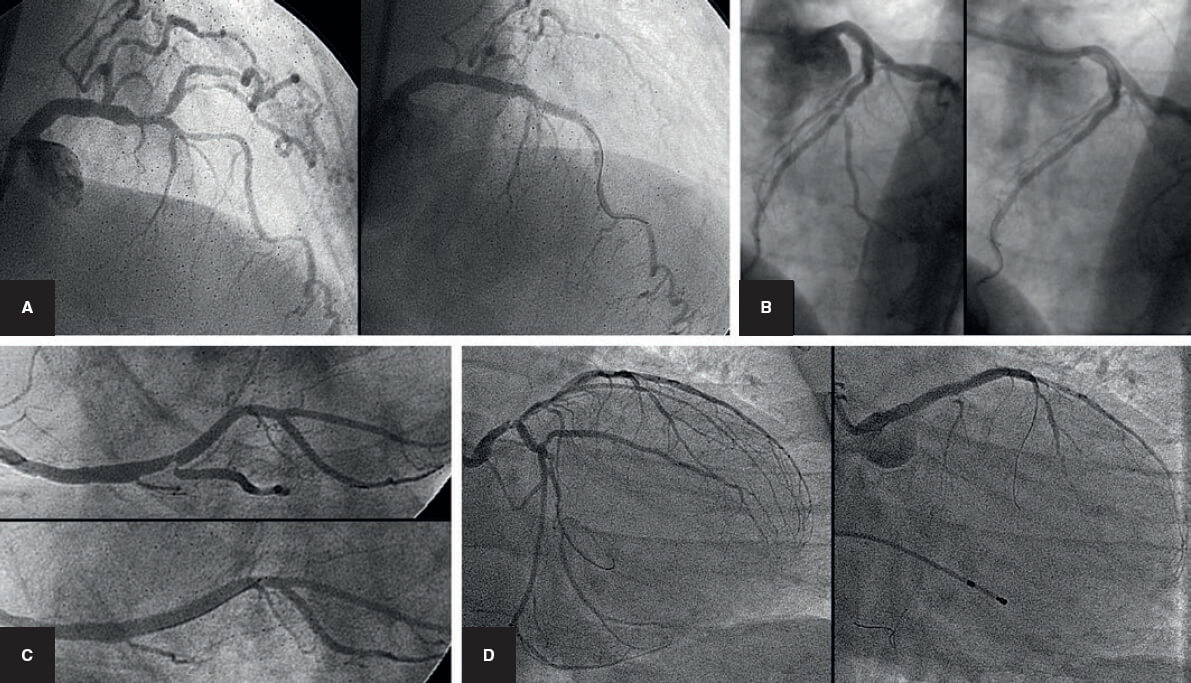

La estrategia del stent provisional se ha llamado «técnica simple», aunque en ocasiones puede no ser tan simple porque la RL puede ocluirse tras el implante del stent en el VP (figura 3). Esta situación, si no se resuelve, conduce a un infarto de miocardio. La técnica de la guía encarcelada se describió para ayudar a resolver esta situación. Consiste en dejar una guía en la RL mientras se implanta el stent del VP. De esta forma queda atrapada entre la pared del vaso y la estructura metálica del stent.

Figura 3. Cuatro ejemplos de oclusión abrupta de la rama lateral tras el implante del stent en el vaso principal. A y B: descendente anterior/diagonal. C: coronaria derecha/descendente posterior. D: tronco común de la coronaria izquierda con cierre de la arteria circunfleja.